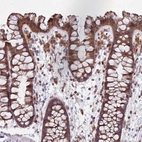

Immunohistochemical staining of human colon shows distinct cytoplasmic and nuclear positivity in glandular cells.